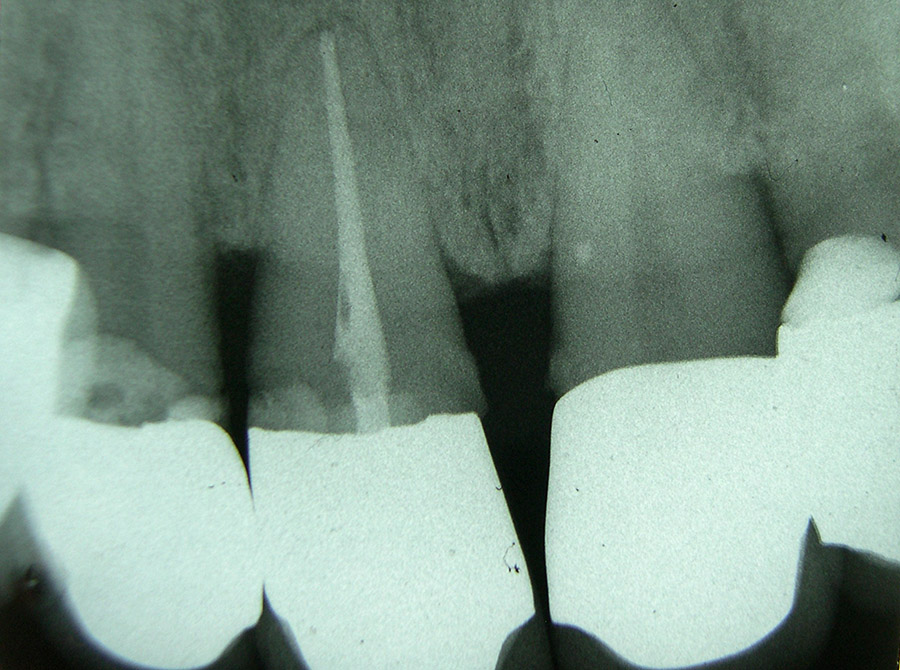

Sonst kann es durch fortschreitende bakterielle Zersetzungsprozesse zu einer Entzündung an der Wurzelspitze des Zahnes kommen, die sich in den Knochen ausbreitet.

Entscheidend für den Langzeiterfolg einer Wurzelkanalbehandlung ist die exakte Füllung des gesamten Wurzelkanals bis zur Wurzelspitze. Daher verlassen wir uns hier nicht nur auf Röntgenbilder, sondern messen mit modernen Zusatzgeräten elektronisch die Länge jedes Wurzelkanals .Die Aufbereitung der Kanäle erfolgt teils von Hand, teils maschinell mit speziell dafür entwickelten, drehmomentbegrenzten Motoren und hochflexiblen Einmal-Feilen. Vor der endgültigen Wurzelfüllung wird bei uns jeder Wurzelkanal laser-sterilisiert, d.h. evtl. noch vorhandene Bakterien werden durch Zufuhr hochenergetischen Laserlichts über flexible Glasfasern abgetötet.